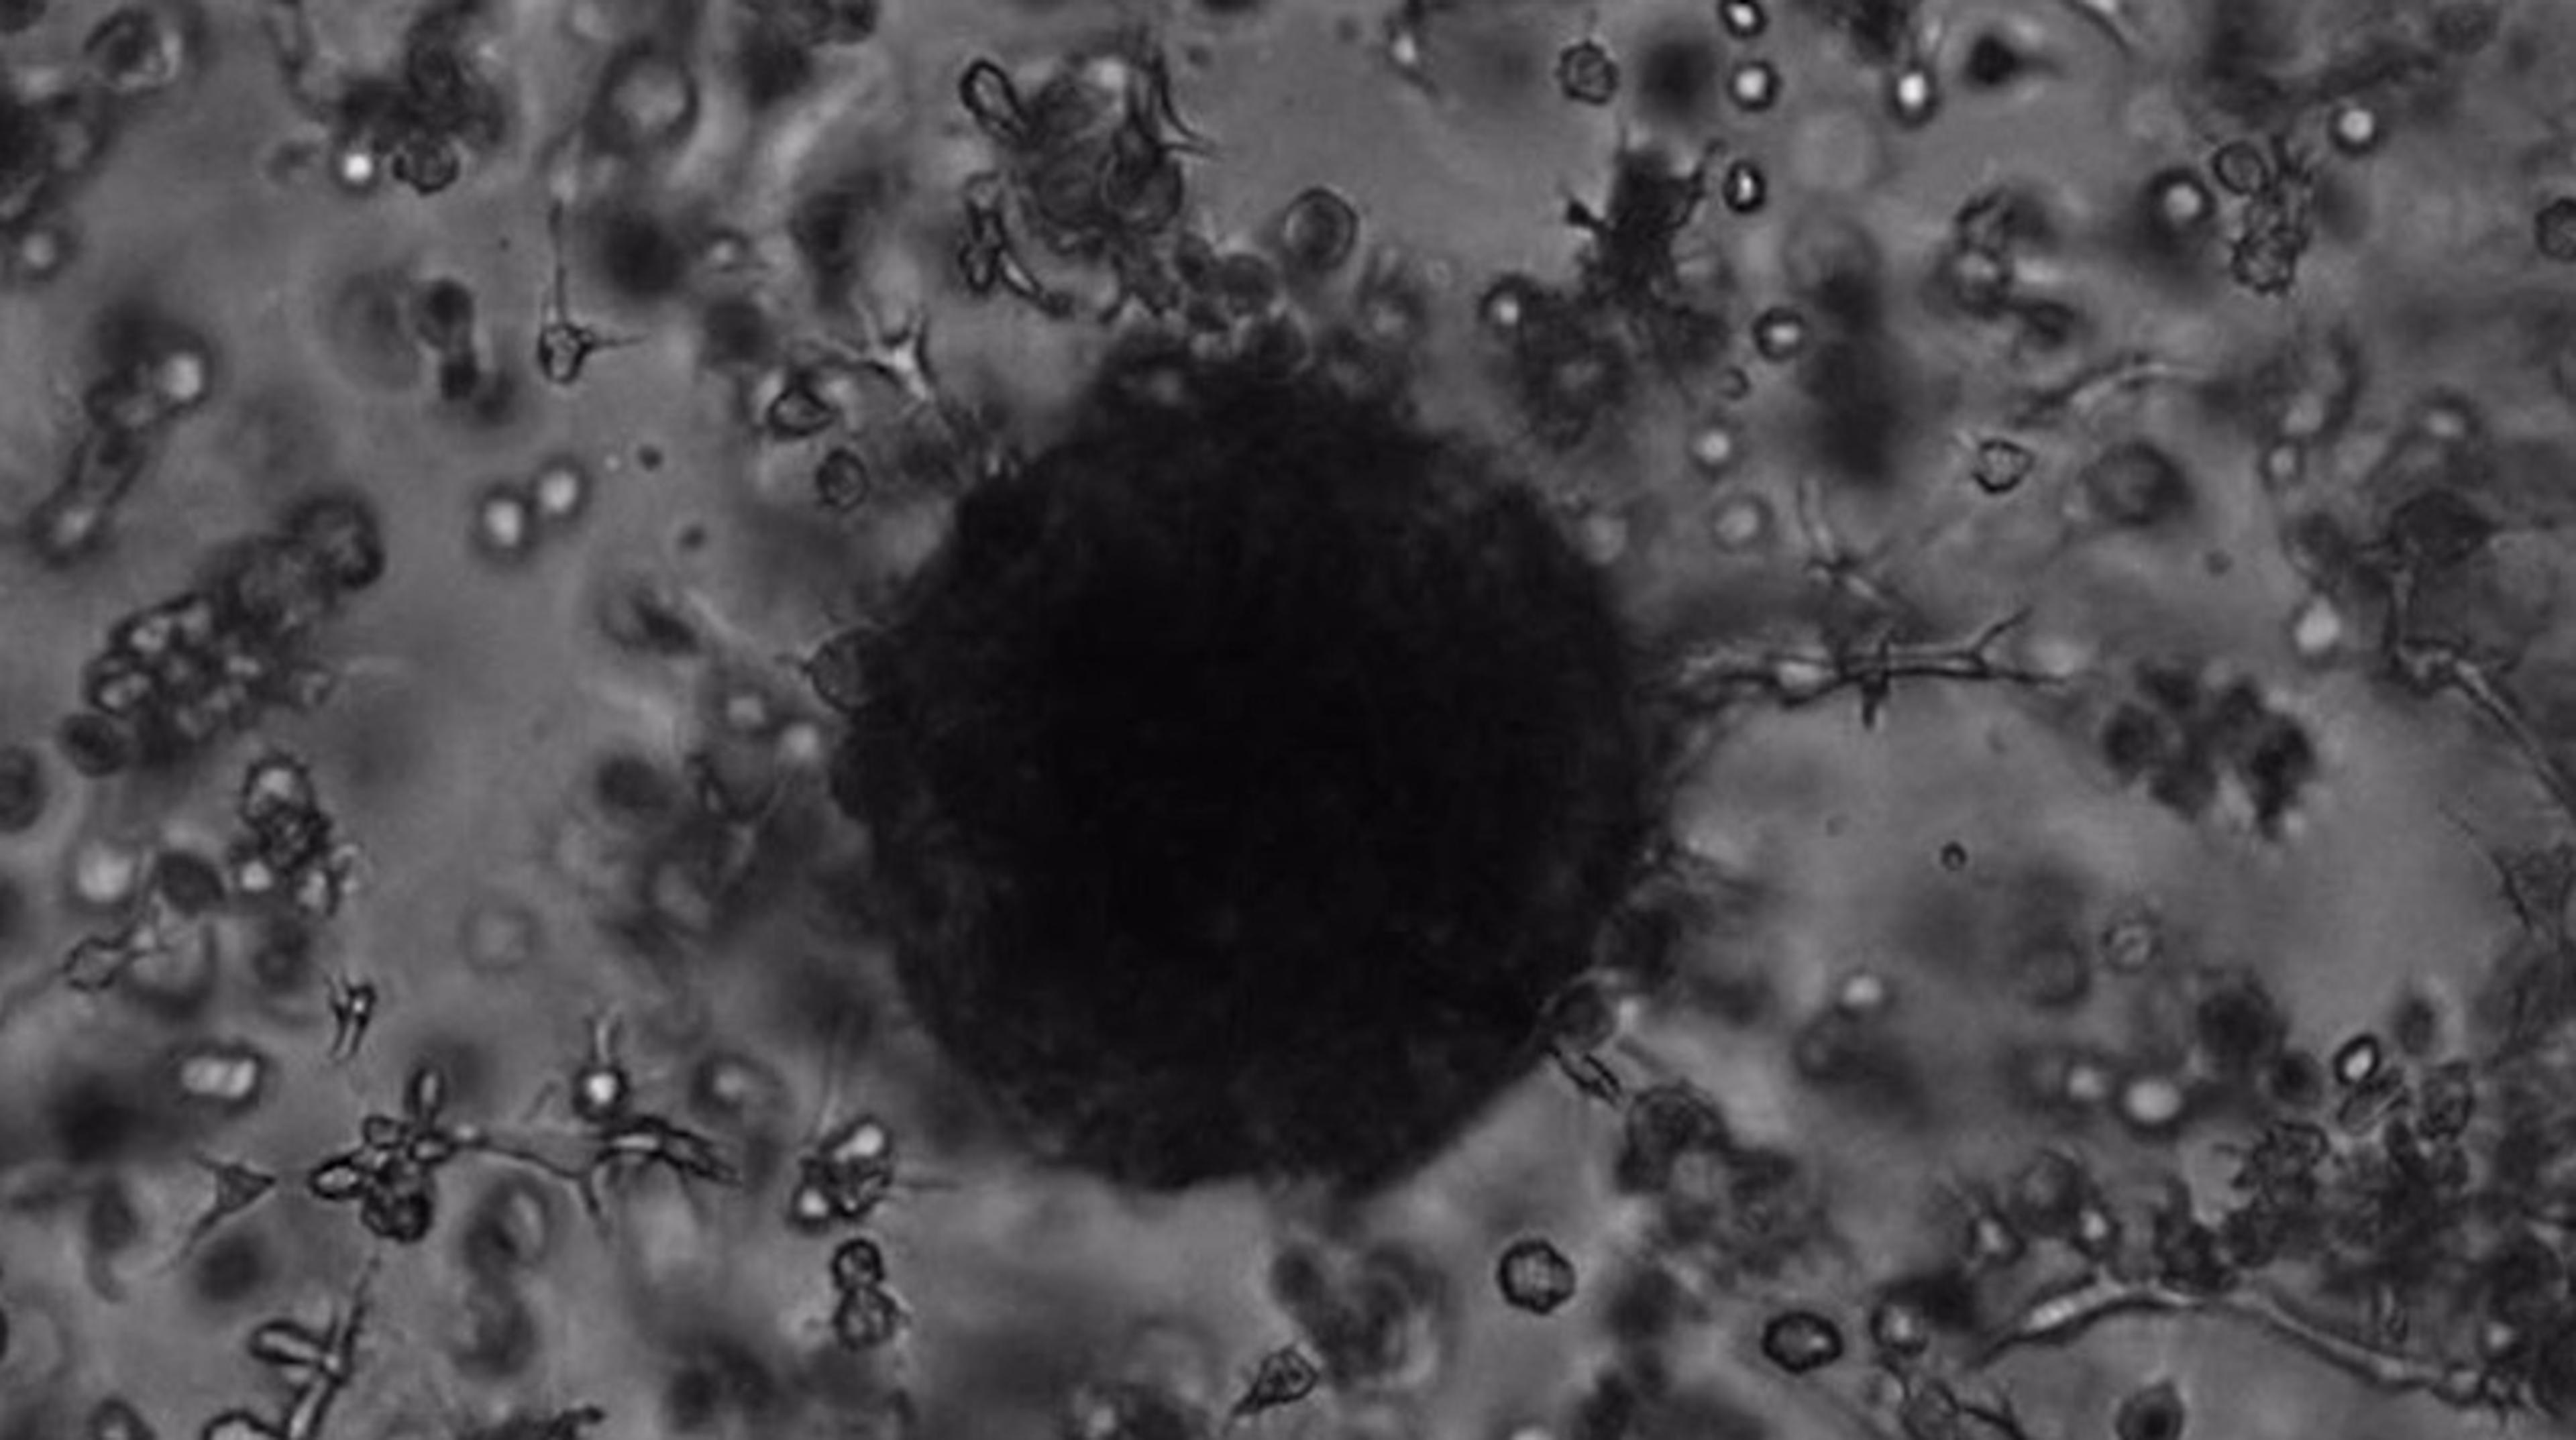

In this video, watch as cancer-associated fibroblasts surround a tumor spheroid, establishing a 3D microenvironment in vitro.

Merck's new TrueGel3D® HTS Hydrogel Plates provide a fully ready-to-use solution for easily establishing 3D cell cultures and co-cultures for screening and imaging applications.